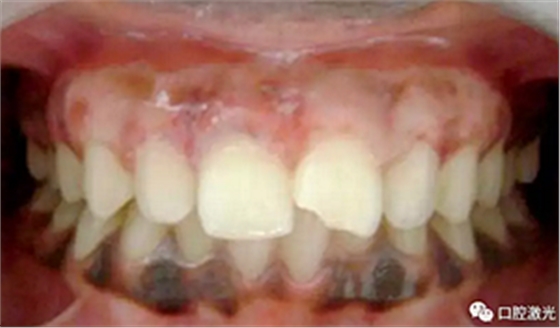

患者术后无明显疼痛不适,没有出现大量出血、感染或结痂现象。整个恢复过程较为顺利。患者接受度高,治疗效果明显。

术后一周

术后三月